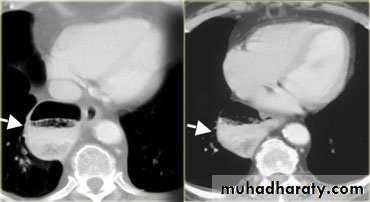

LEFT: CT shows dilated esophagus (arrow) that led to esophagram.RIGHT: Esophagram shows narrowing (arrow) at level of hiatus.